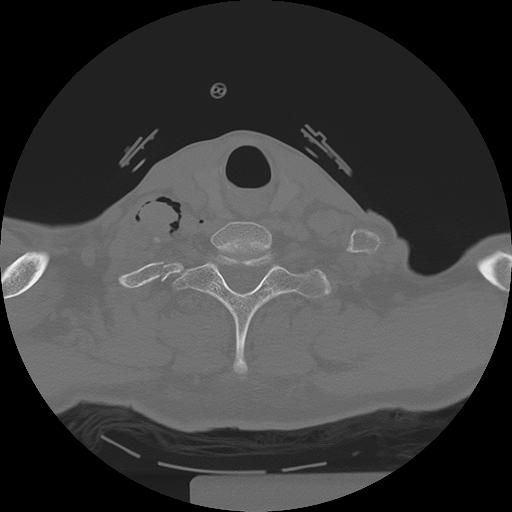

11 HUESO,,Axial,2.0,HUESO,,